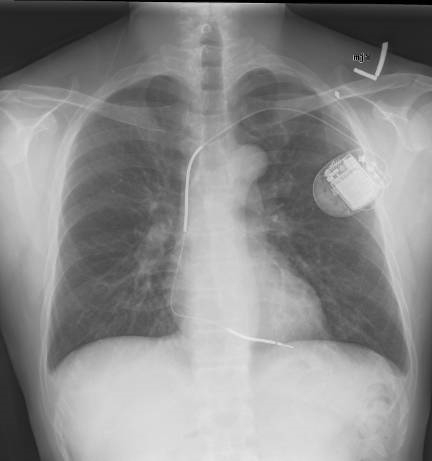

Multiple types of devices exist. Traditional ICDs are inserted transvenously and may have one or more leads. (See Figure 1.) Single-chamber devices have one ventricular lead that both senses and provides therapy (electrical shocks) at the ventricular level. Dual-chamber devices have an additional lead in the atrium that senses atrial activity. A third type of device is a biventricular device with an additional lead that provides cardiac resynchronization therapy (CRT-D).3 Subcutaneous ICDs without transvenous leads have been developed and are under investigation as an option for specific patient populations without need for an artificial pacemaker.6 Importantly, these devices can only deliver shocks and cannot perform ATP.

Figure 1. Implantable Cardioverter Defibrillator |

![]() |

Source: Gregory Marcus, MD, MAS, FACC. Wikimedia Commons https://creativecommons.org/licenses/by/3.0/deed.en. |